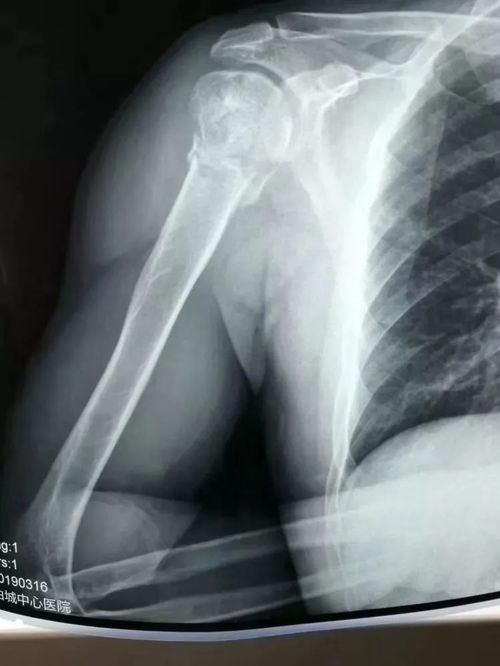

粉碎性骨折,当骨头碎成渣时,我们如何应对?

粉碎性骨折,听起来是不是有点吓人?但其实,这并不是什么罕见的事情,它是一种严重的骨折类型,骨头不仅断裂,还碎成了多块,就像那块不幸的巧克力,骨头的完整性被破坏,需要专业的医疗干预来恢复。

治疗粉碎性骨折通常需要手术,医生会使用金属板、钉子或者螺丝来固定骨头的碎片,帮助它们重新连接和愈合,这个过程就像是用胶水和胶带把碎掉的巧克力重新拼凑起来,虽然不能完全恢复原状,但至少可以让它保持一定的形状和功能。